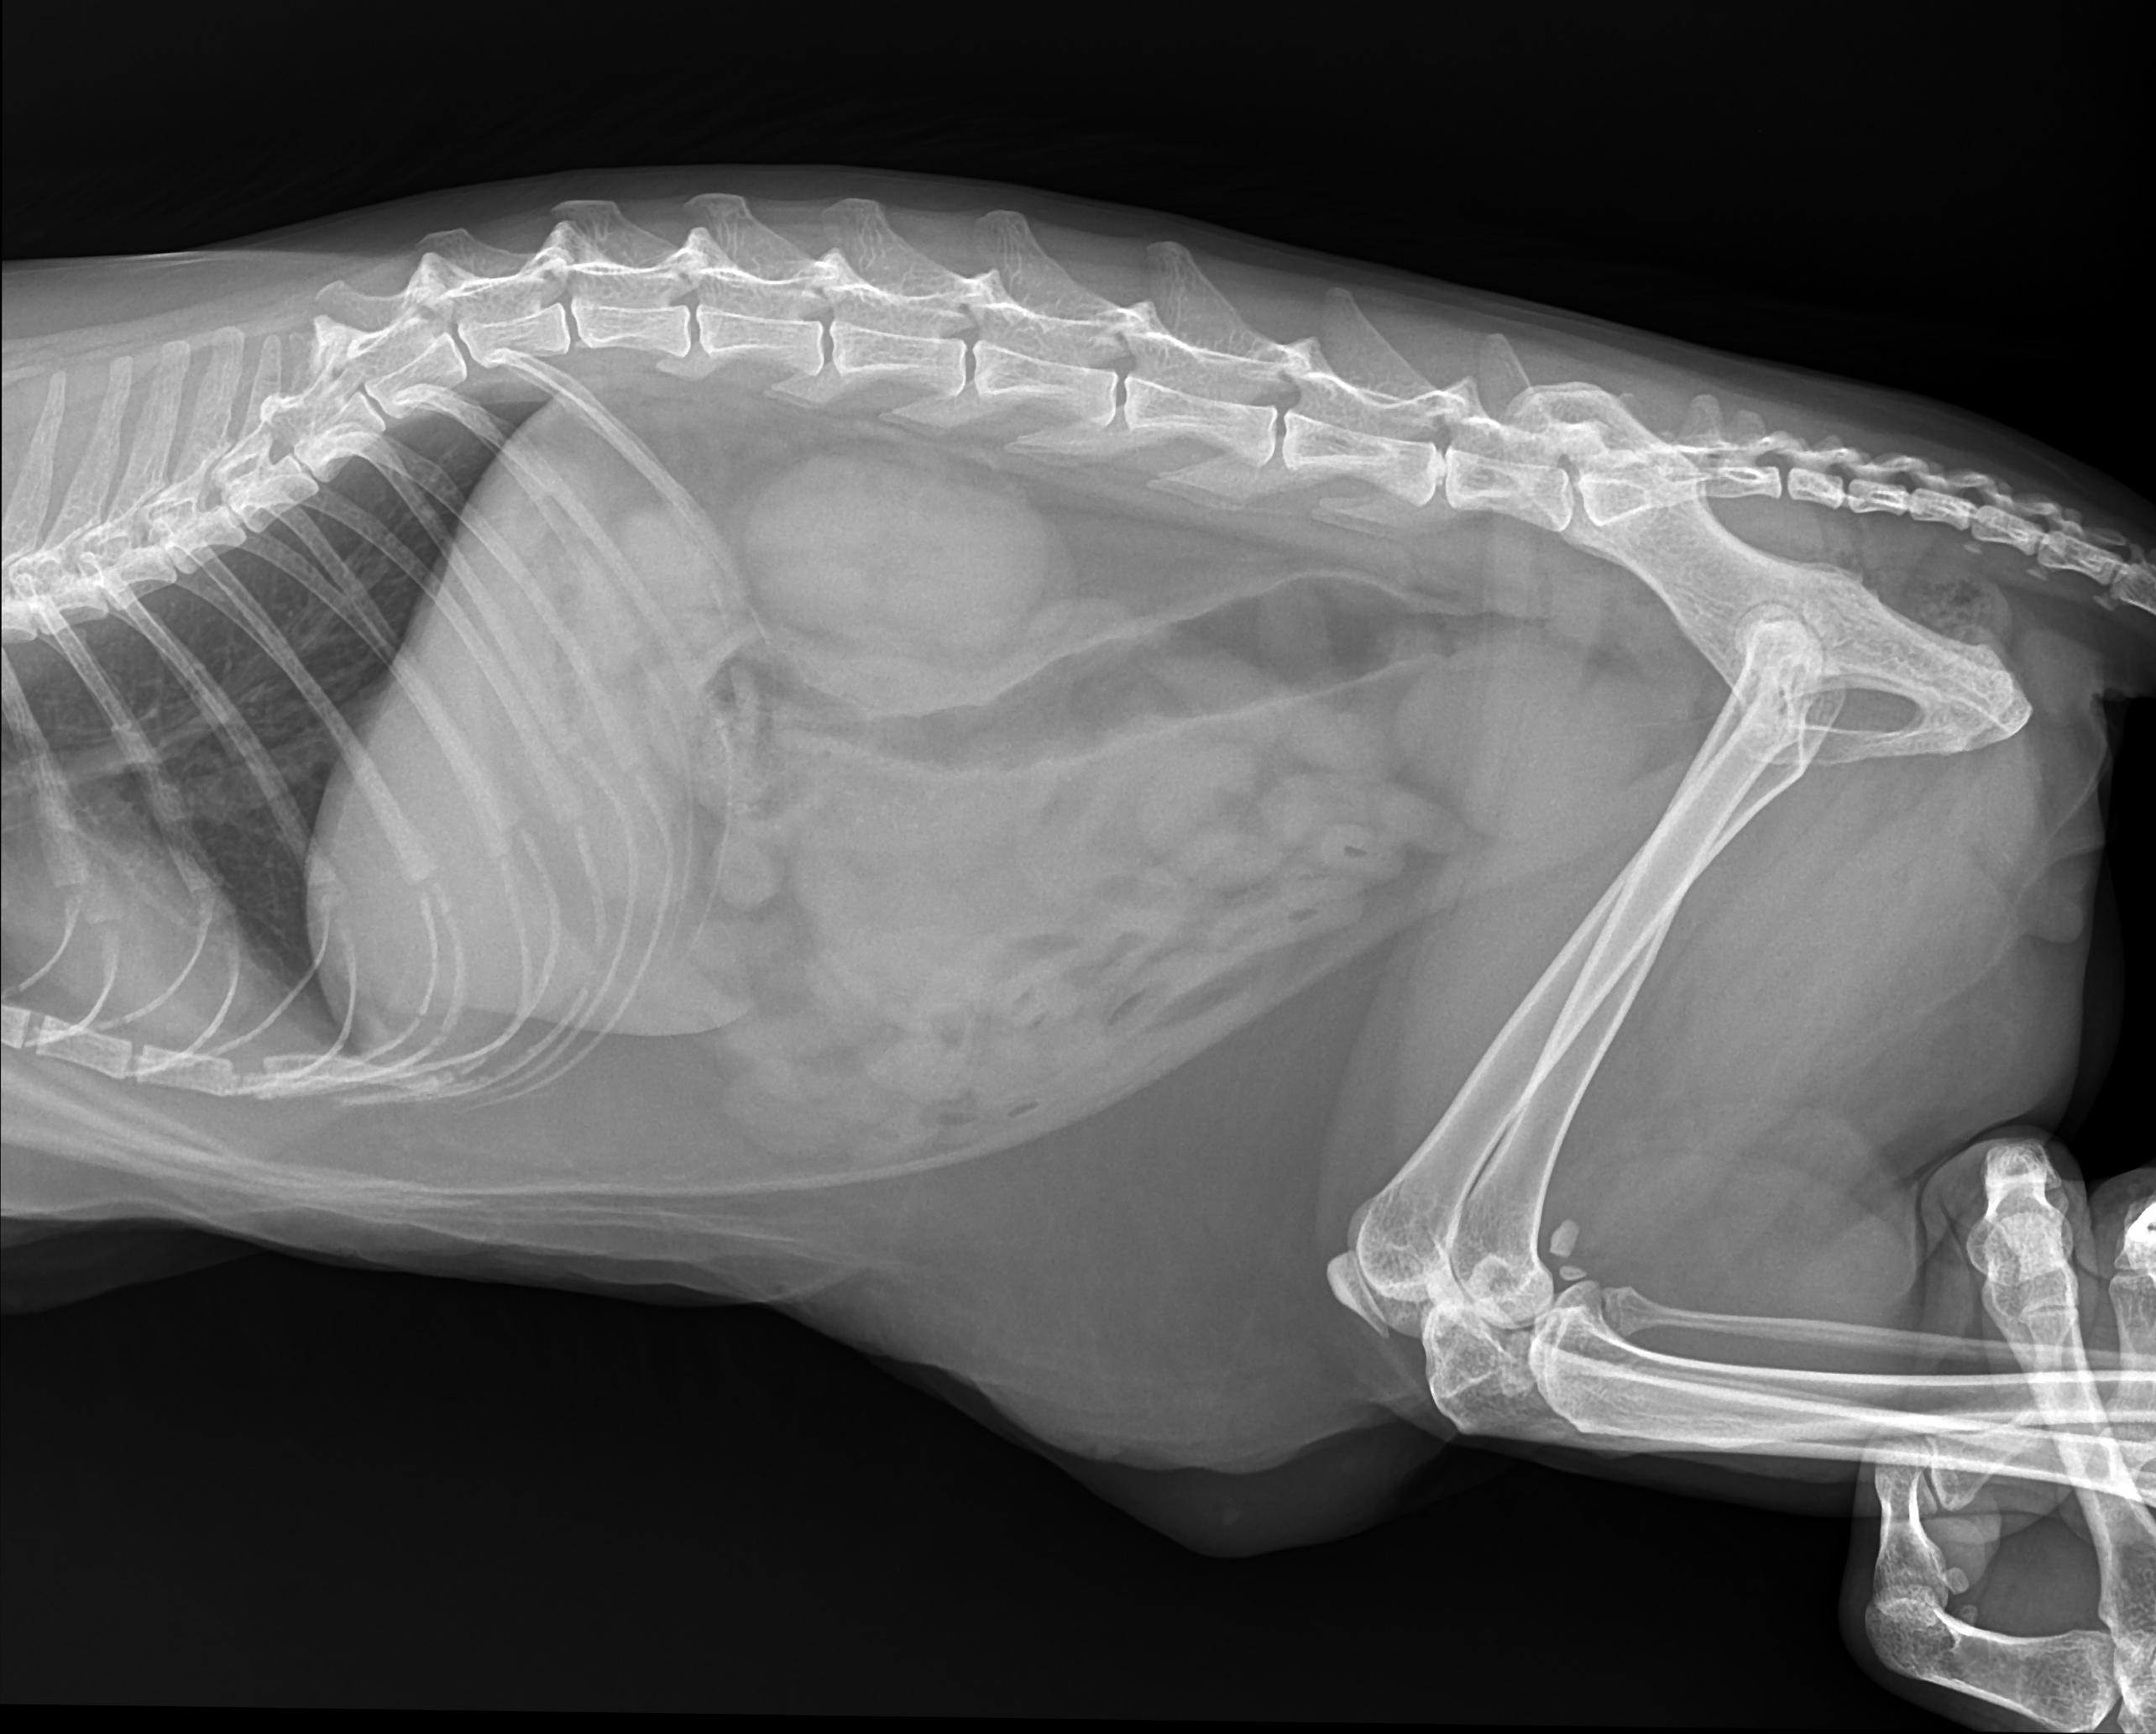

Рентгеновские снимки головы кошки в боковой проекции